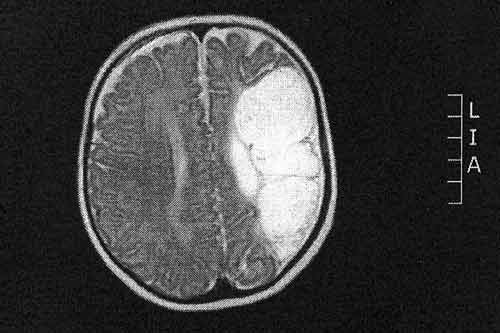

| Phim chụp Xquang gần một nửa bộ não của Jake, phần màu trắng gần như bị khuyết trước khi sinh. |

Tại bệnh viên, các bác sĩ đã kiểm tra và thông báo rằng bé Jake đã bị u não khiến gần một nửa não bộ của em bị khuyết trước khi sinh ra.

Các bác sĩ tin rằng lúc Jake còn trong dạ con thì đã bị thiếu oxy cung cấp cho não. Khối u đã phát triển tại nơi não bị tổn thương.